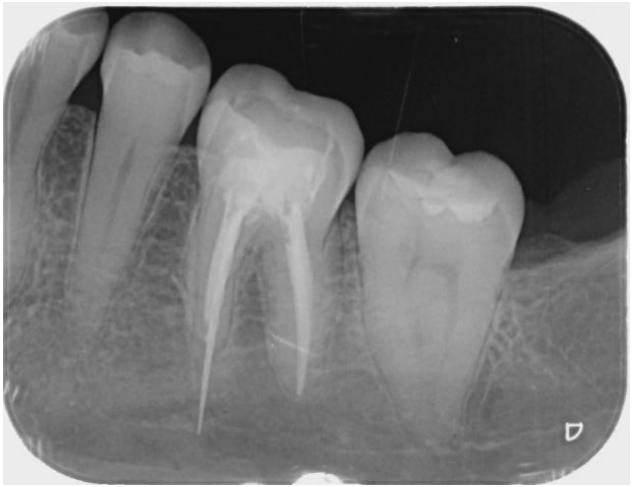

Fractured endodontic instruments are a common complication in root canal therapy, often leading to treatment failure and ongoing patient discomfort. This case involves a patient referred by a colleague approximately four months after the initial incident of instrument fracture during endodontic therapy. The fractured instrument was located in the mesiobuccal canal of a left lower molar, extending 8 mm beyond the apex.

To assess the extent of the fracture and plan for removal, we obtained periapical radiographs and a cone-beam computed tomography (CBCT) scan. The imaging revealed the fractured NiTi instrument lodged deep within the canal system, complicating its retrieval due to its position approximately 8 mm beyond the apical foramen.

Figure 1